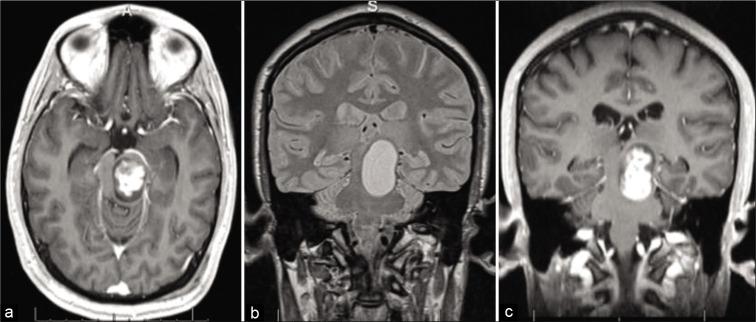

This report describes a case of a 22-year-old male, who presented with progression of a primary brainstem tumor previously treated with stereotactic radiosurgery and chemotherapy. Patient underwent surgical exploration and was diagnosed with juvenile PA, but debulking was limited by the very dense and fibrous tumor. Complete surgical resection was not possible at this time. Despite efforts to treat with chemotherapy, the patient presented a year later with clinical deterioration and severe neurologic deficits, prompting surgical re-exploration. During the second operation, the tumor was found to have undergone very significant softening in consistency, allowing for gross total resection (GTR).

本报告描述了一名22岁男性病例,该患者曾接受立体定向放射外科和化疗,现原发性脑干肿瘤出现进展。患者接受了手术探查,被诊断为青少年型PA,但由于肿瘤质地非常致密且呈纤维状,减瘤手术受限。此时无法进行完全手术切除。尽管进行了化疗,但患者在一年后出现临床病情恶化和严重神经功能缺损,促使再次进行手术探查。在第二次手术中,发现肿瘤质地已显著变软,从而得以进行全切除(GTR)。